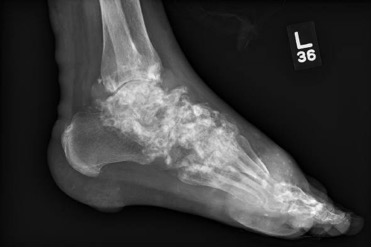

Case Presentation: A 40-year-old man with a history of severe tophaceous gout, not currently on treatment, was directly admitted to the hospital after routine labs showed hypercalcemia (14.1mg/dL) and an elevated creatinine (4.2mg/dL). Vital signs were stable. Exam was significant for large nodules and tophi across most joints, with innumerable subcutaneous nodules embedded in the skin of his arms, legs, flanks and buttocks (Figure 1). The workup of hypercalcemia was systematically approached. First, we determined that the cause was parathyroid-independent, given an appropriately low PTH (11.1 pg/mL). Next, malignancy and granulomatous disease were ruled out with a negative CT scan of the chest, abdomen, and pelvis. A PTH-related protein (PTH-rp), secreted by solid tumor malignancies, and UPEP, SPEP, and light chains, elevated in hematologic malignances, were drawn and all normal. Skin biopsy ruled out cutaneous T-cell lymphoma.Next, TSH and vitamin A level were found to be normal. Finally, a 1,25 dihydroxy-vitamin D was drawn and found to be elevated (85.9 pg/mL), giving us a potential clue. Bilateral hand and foot x-rays showed extensive, calcified tophaceous gout with erosions and bone loss (Figure 2). Skin biopsies showed focal calcifications of amorphous material surrounded by mononuclear histiocytes, giant cells, and fibrosis. After a detailed discussion with consultants, the most likely cause of this patient’s severe hypercalcemia was a chronic granulomatous reaction driven by tophaceous gout.